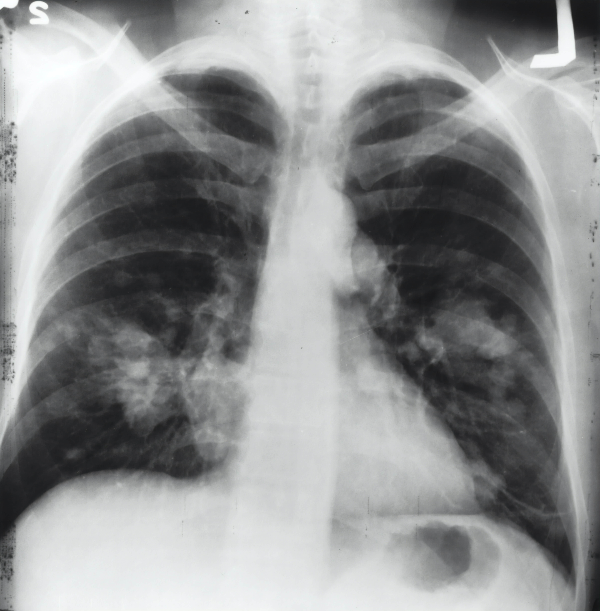

폐 결절은 이전에 발생한 폐렴이나 결핵과 같은 감염을 비롯하여 다양한 원인에 의해 발생할 수 있습니다. 실제로, 폐 결절을 가진 사람 중 상당수는 어떤 질병도 없습니다. 그러나 가끔씩 폐 결절은 암의 징후일 수 있기 때문에, 폐 결절을 정확하게 평가하는 것이 중요합니다. 폐 결절 평가를 위해 의사는 일반적으로 CT 스캔, PET 스캔, 혹은 직접적인 생검 등을 수행합니다.

감염은 폐 결절의 원인 중 하나일 수 있습니다. 세균, 바이러스 또는 기타 감염원은 폐 조직 내에서 염증을 유발할 수 있으며, 결절 형성의 원인이 될 수 있습니다. 결핵이나 폐렴과 같은 감염성 질환은 폐 결절의 발생을 촉진시킬 수 있는 요소입니다.

폐 결절의 진단과 치료는 그 크기, 수, 위치, 그리고 악성 변화 가능성에 따라 다르게 결정됩니다. 폐 결절이 발견되면, 의사는 추가적인 검사를 시행할 수 있습니다. 폐 결절에 대한 최종 진단은 생검을 통해 이루어지며, 악성 종양일 경우 수술적 치료나 방사선 치료 등의 치료가 필요할 수 있습니다.